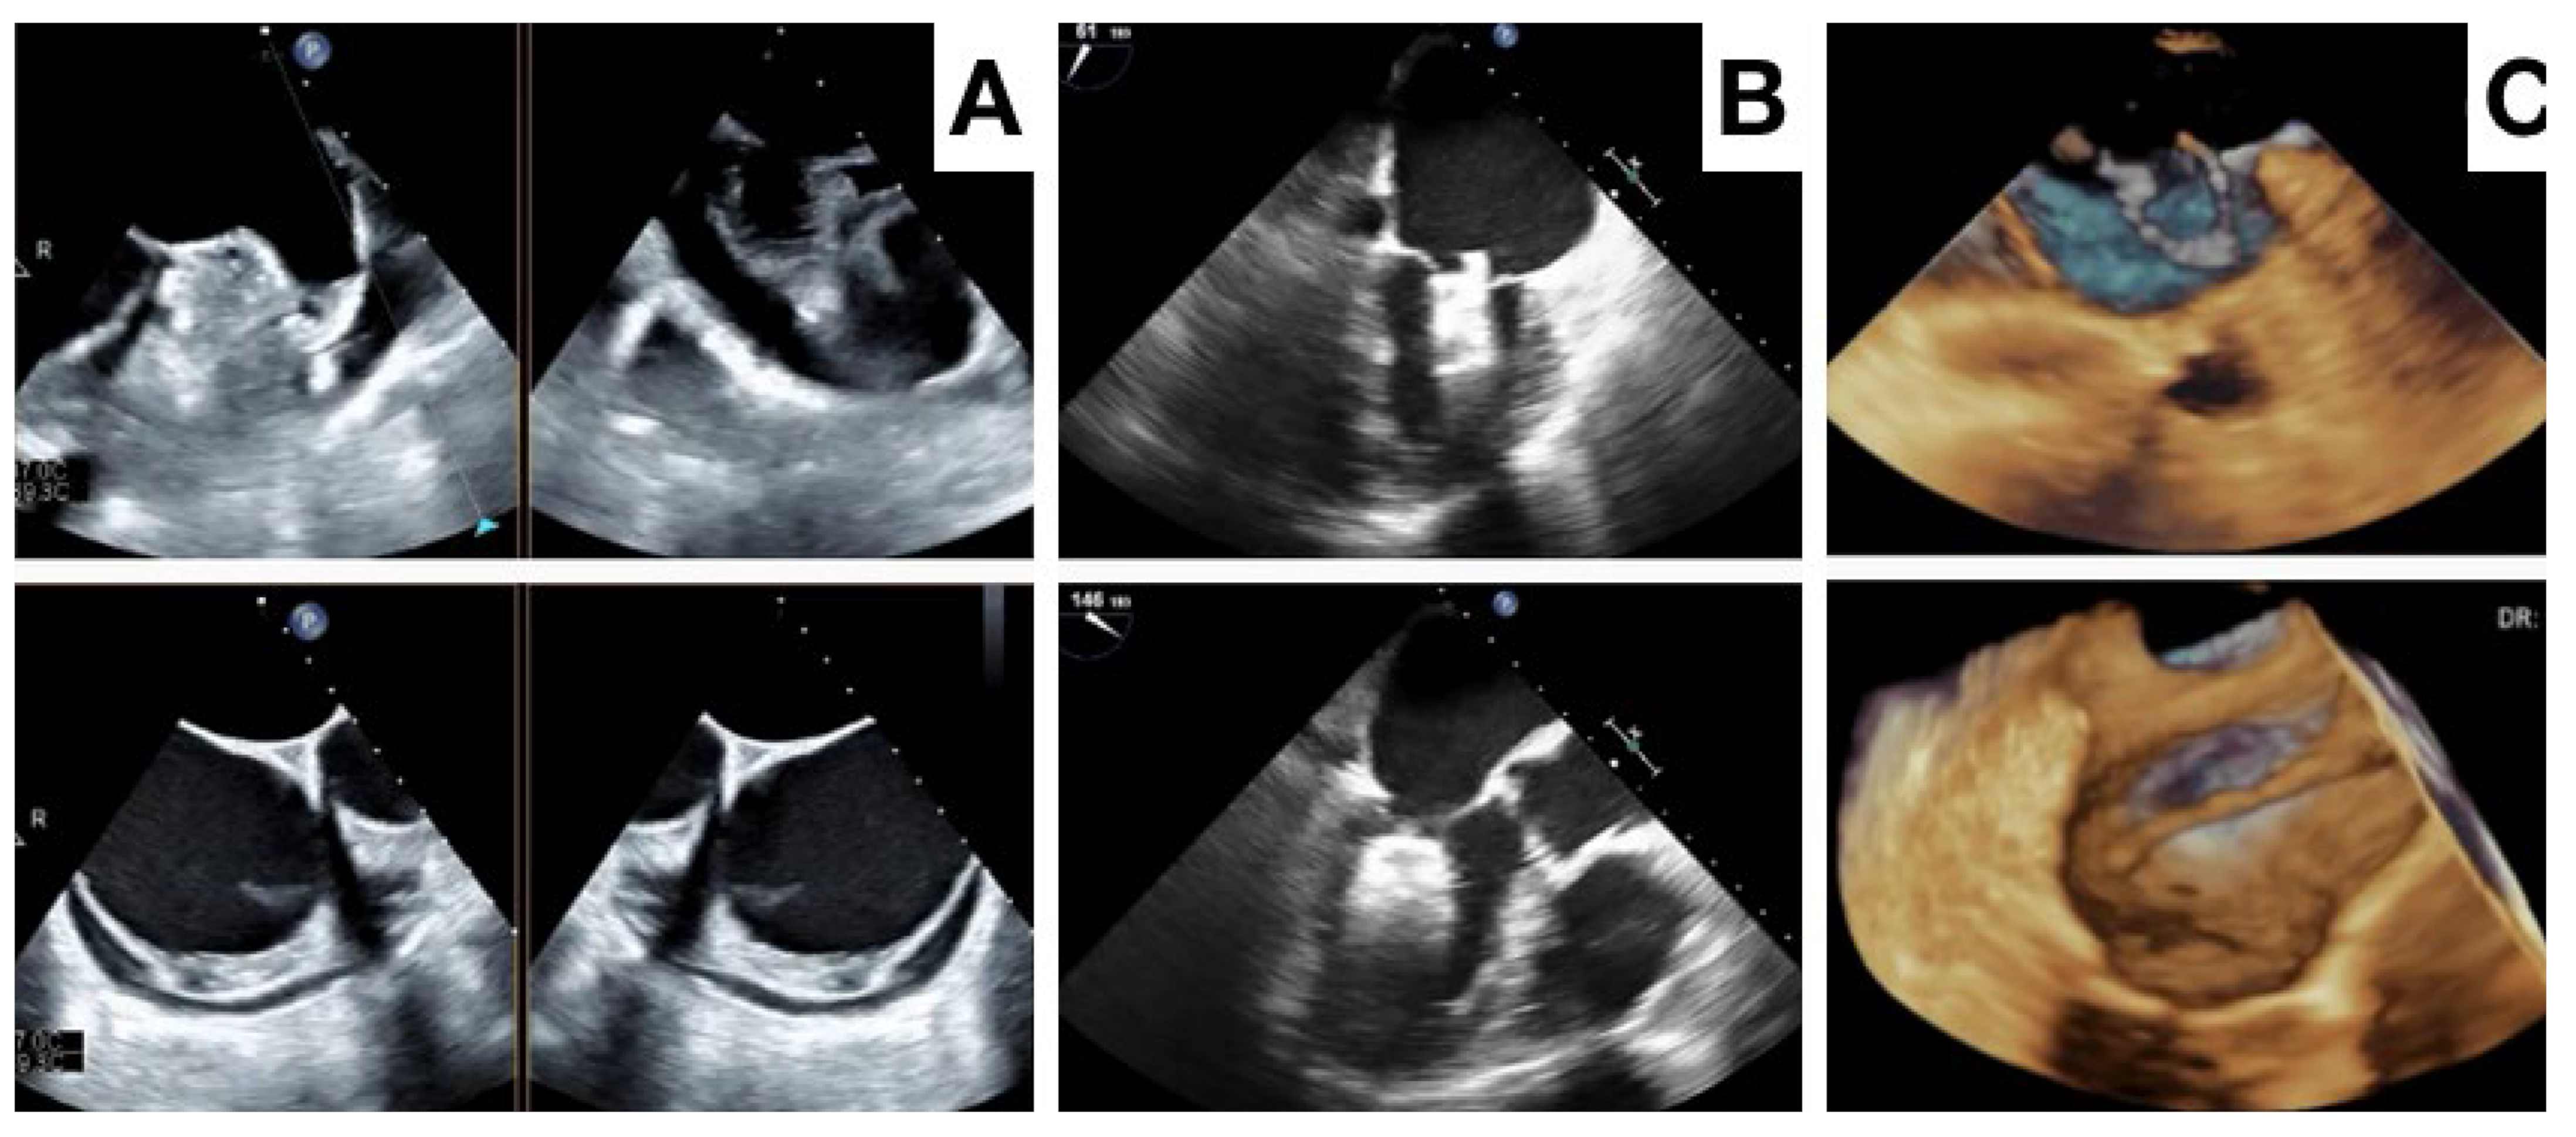

- Dukkipati, S.R.; Kar, S.; Holmes, D.R.; Doshi, S.K.; Swarup, V.; Gibson, D.N.; Maini, B.; Gordon, N.T.; Main, M.L.; Reddy, V.K. Device-related thrombus after left atrial appendage closure. Circulation 2018, 138, 874–885. [Google Scholar] [CrossRef] [PubMed]

- Alkhouli, M.; Busu, T.; Shah, K.; Osman, M.; Alqahtani, F.; Raybuck, B. Incidence and clinical impact of device-related thrombus following percutaneous left atrial appendage occlusion: A meta-analysis. J. Am. Coll. Cardiol. EP 2018, 4, 1629–1637. [Google Scholar] [CrossRef] [PubMed]

- Korsholm, K.; Jensen, J.M.; Nørgaard, B.L.; Nielsen-Kudsk, J.E. Detection of Device-Related Thrombosis Following Left Atrial Appendage Occlusion: A Comparison Between Cardiac Computed Tomography and Transesophageal Echocardiography. Circ. Cardiovasc. Interv. 2019, 12, e008112. [Google Scholar] [CrossRef] [PubMed]

- Simard, T.; Jung, R.G.; Lehenbauer, K.; Piayda, K.; Pracoń, R.; Jackson, G.G.; Flores-Umanzor, E.; Faroux, L.; Korsholm, K.; Chun, J.K.R.; et al. Predictors of Device-Related Thrombus Following Percutaneous Left Atrial Appendage Occlusion. J. Am. Coll. Cardiol. 2021, 78, 297–313. [Google Scholar] [CrossRef] [PubMed]

- Samaras, A.; Papazoglou, A.S.; Balomenakis, C.; Bekiaridou, A.; Moysidis, D.V.; Patsiou, V.; Orfanidis, A.; Giannakoulas, G.; Kassimis, G.; Fragakis, N.; et al. Residual leaks following percutaneous left atrial appendage occlusion and outcomes: A meta-analysis. Eur. Heart J. 2024, 45, 214–229. [Google Scholar] [CrossRef]